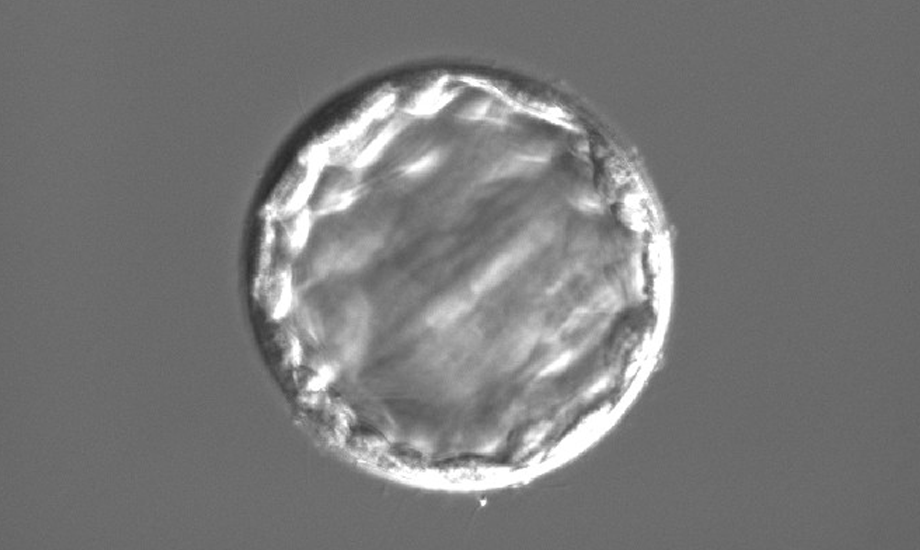

受精卵を囲んでいる透明帯が硬かったり、厚かったりしますと、成長しづらくなり、着床しにくくなります。

アシステッドハッチングとは、透明帯を薄くし、着床率を向上させる方法です。